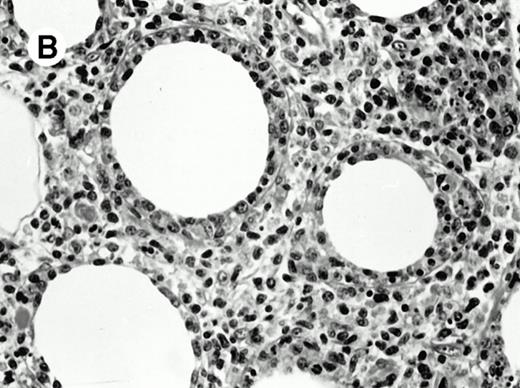

All cases were studied for cytotoxic markers. All of them demonstrated a strong granular cytoplasmic positivity for the cytotoxic granule-associated protein TIA-1. A variable proportion of neoplastic cells were also found positive with Granzyme B (Fig 4A and B) in all cases. Staining for perforin was performed on frozen sections in nine cases, of which seven were positive, one was negative, and the remaining was not interpretable.

Granzyme B expression. (A) Strong paranuclear staining of neoplastic cells in a nasal lymphoma (case no. 3); (B) strong cytoplasmic staining of a few neoplastic cells surrounding intestinal glands in an enteropathy-associated γδ T-cell lymphoma (case no. 11). (Paraffin-embedded section, APAAP technique.)